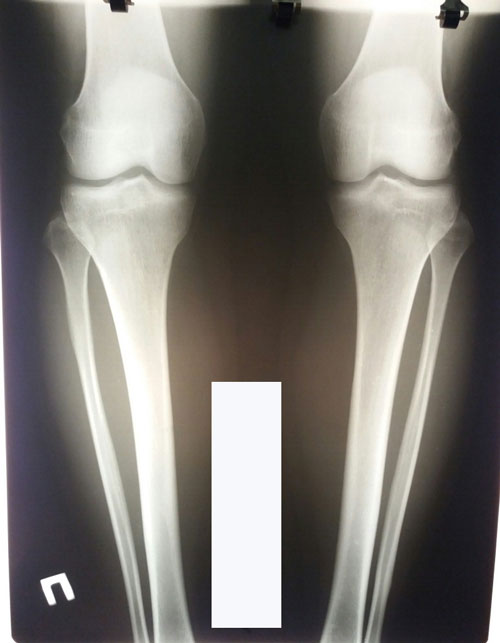

Исходник - 28 лет. Петропавловск.

Дата операции 09.07.2018г.

Дата снятия аппаратов 24.09.02018г.

Срок сращения 75 дней.